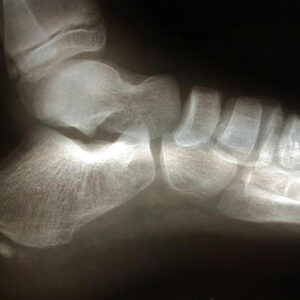

Kids generally experience heel pain which is a form of foot pain. Although, not serious, it still requires proper diagnosis and prompt treatment. If your child complains about heel pain and tenderness in the foot or ankle, which makes them limp uncontrollably, they might be experiencing some kind of foot injury.